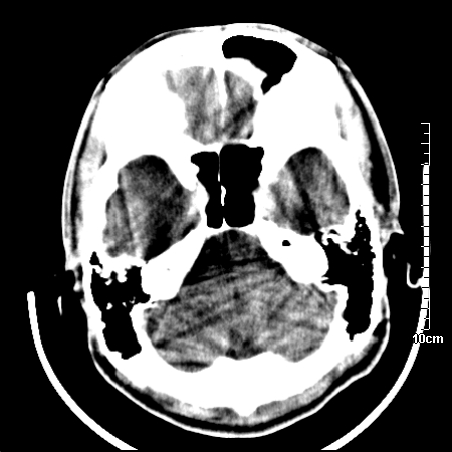

病人在家输液时出现发热.头痛.恶心等不适

右侧放射冠区混杂密度灶,边缘不清,病人较年轻,结合有发热病史,支持感染性病变,建议密切结合临床可抗感染治疗后复查。

右侧颞叶病变定性困难,既然发病急,又有发热,脑脓肿不能除外。